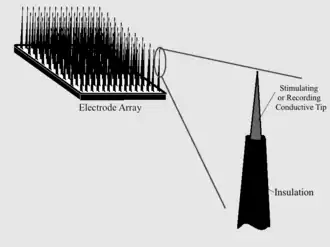

Input Electrode

Intracranial electrodes is composed of conductive electrode arrays implanted on a polymer or silicon, or a wire electrode with an exposed tip and insulation for the part that stimulation or recording is not needed.

Current implantable microelectrodes could not record single- or multi-unit activity depending on a chronic scale. Lebedev and Nicolelis reviewed the specific needs in the field to truly improve the technology to the level of clinical implementation. In short, the 4 requirements in their review are:

- Consistent long term (over the years) recording of large neuronal populations in multiple brain areas;

- Efficient processing of recorded data;

- Incorporation of feedback into the user’s body using native plasticity;

- Advances in prosthetic technology to create artificial limbs which can reproduce the full motion.[37][38]